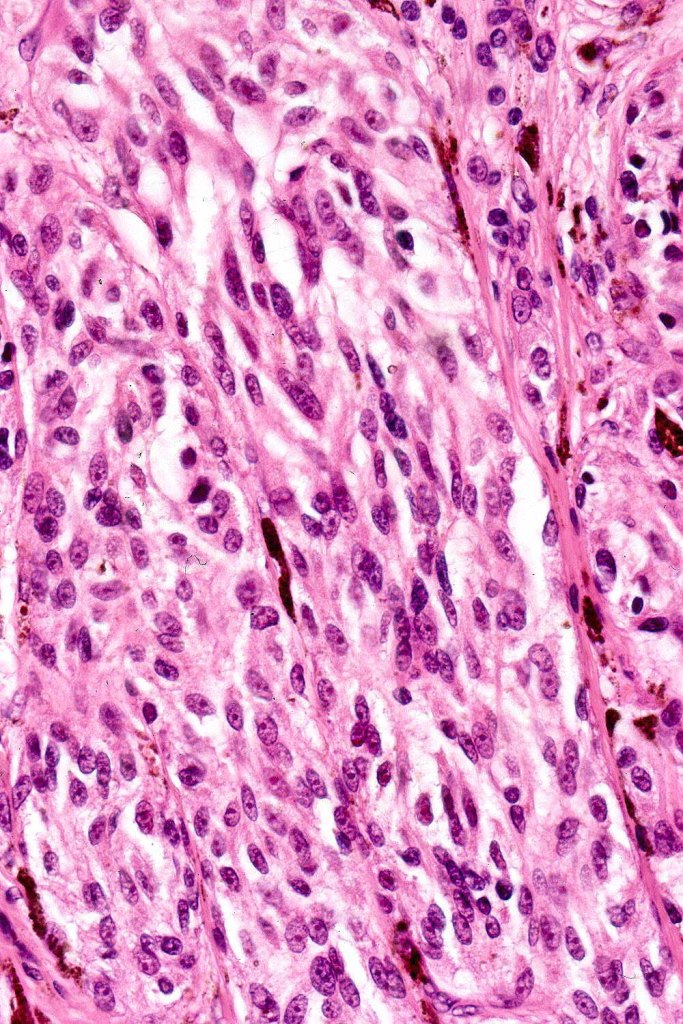

Histological features

•Symmetrical, circumscribed wedge-shaped infiltrate-most common growth pattern with the broad base uppermost, deeper aspect extends along appendageal structures & neurovascular bundles with a fasciular or plexiform pattern

•Superficial epithelioid cells

•Deep spindle cells